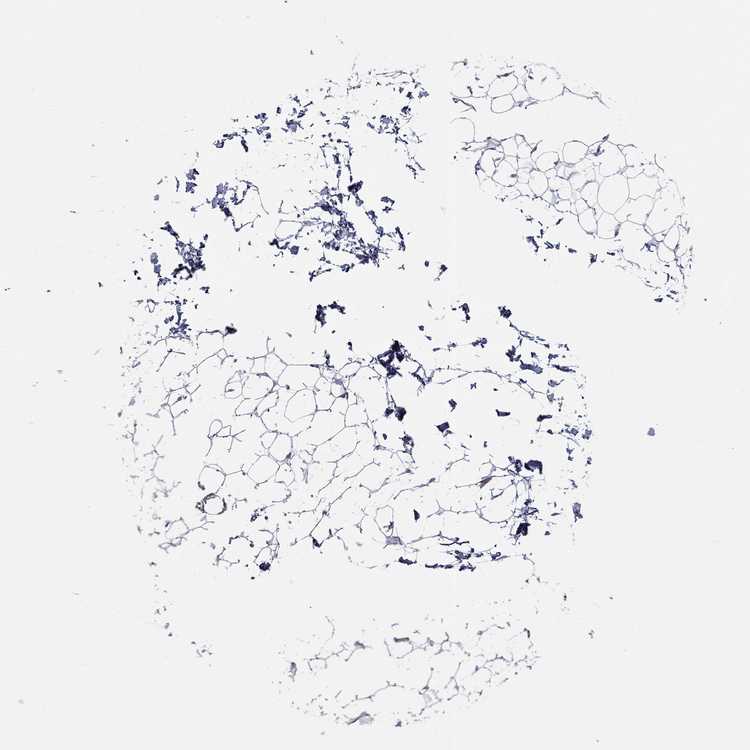

ADIPOSE TISSUE - Antibody stainingi

Antibody staining in the annotated cell types in the current human tissue is reported as not detected, low, medium, or high, based on conventional immunohistochemistry profiling in selected tissues. This score is based on the combination of the staining intensity and fraction of stained cells.

Each image is clickable and will lead to virtual microscopy that enables deeper exploration of all samples and also displays staining intensity scores, fraction scores and subcellular localization as well as patient and tissue information for each sample.

Antibody HPA011140

Adipocytes Not detected